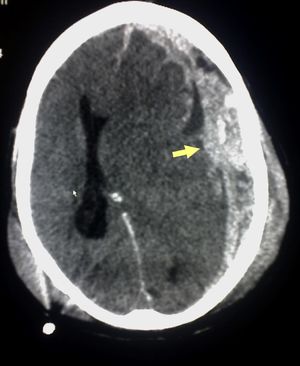

Appearance on CT | Biconvex lens | Crescent-shaped |

يعتمد رئيساً على تصوير الدماغ (التصوير الطبقي المحوري والرنين المغنطيسي MRI)، وفيه يظهر النزف عادة على شكل تجمع هلالي بين الجمجمة والدماغ.

يختلف العلاج باختلاف حجم النزف وسرعة تشكله والأعراض الناتجة منه. ففي بعض حالات النزف المزمن قد تكفي المعالجة الدوائية (مثل إعطاء مضادات الاختلاج، وإيقاف مميعات الدم)، أما في حالات أخرى مثل النزف تحت الجافية الحاد الذي تزيد سماكته عن سنتمتر واحد فينبغي تفريغه جراحياً.